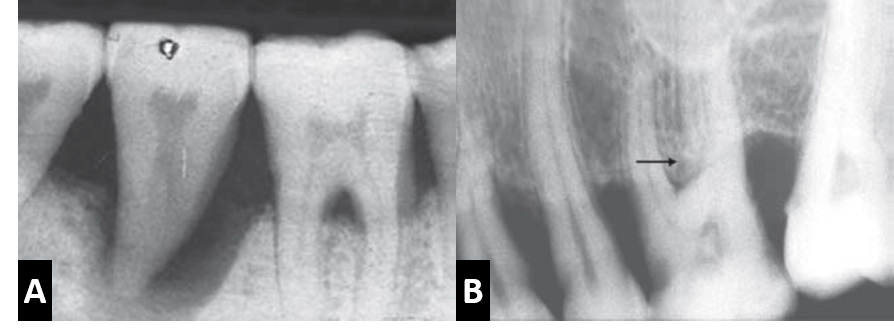

Las radiografías pueden llegar a detectar signos tempranos de la enfermedad periodontal, como la irregularidad de la cresta o la perdida ósea a nivel interseptal debido al aumento del ensanchamiento de los canales nutricios. Así mismo, la cresta ósea se presenta irregular y con interrupción de la integridad de la lámina dura por mesial y distal del hueso alveolar interdental. Otro signo temprano es la triangulación, que se define como el ensanchamiento del espacio periodontal, con sus lados formados por la lámina y la superficie radicular con su base hacia coronal.

Entre los factores predisponentes de enfermedad periodontal observables radiográficamente, se pueden observar irritantes locales como los cálculos o las restauraciones defectuosas. Los cálculos dentales corresponden a placa bacteriana acumulada y calcificada, las cuales se pueden observar como espículas irregulares radiopacas a nivel cervical por mesial o por distal; o pueden ser observadas también rodeando un diente en su zona cervical como un anillo radiopaco, sin embargo, pequeños depósitos de cálculos pueden pasar desapercibidos en una radiografía.